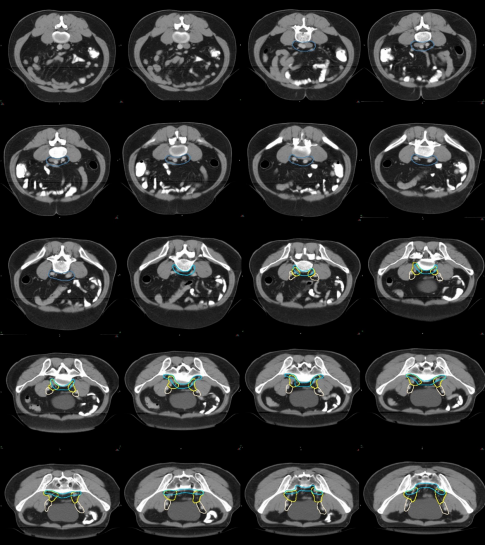

i) 高危復發區合集圖(CT 層厚 0.5 cm,俯臥位)(圖 14)。下表 示出高危復發區顏色。

表 直腸癌高危復發區顏色

圖 14 直腸癌高危復發區合集圖